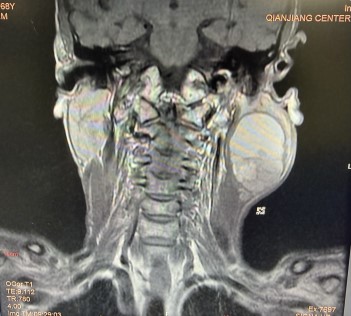

经检查,肿瘤已占据王先生整个腮腺区,体积巨大且位置极深。肿瘤短期内快速增大,还导致局部正常解剖结构严重紊乱、组织水肿,使得手术如同在“雷区”中排爆,风险极高。稍有不慎,都可能导致大出血、脑梗塞、声音嘶哑、吞咽困难等严重后果。

手术当日,凭借丰富的临床经验和娴熟的显微外科技术,手术团队沉心静气,在错综复杂的组织中抽丝剥茧,逐层分离。经过数小时的精细操作,最终成功地将肿瘤与面神经、颈内动脉等重要结构完整、清晰地分离开,实现了肿瘤的根治性切除,同时完好地保留了患者的面神经功能。